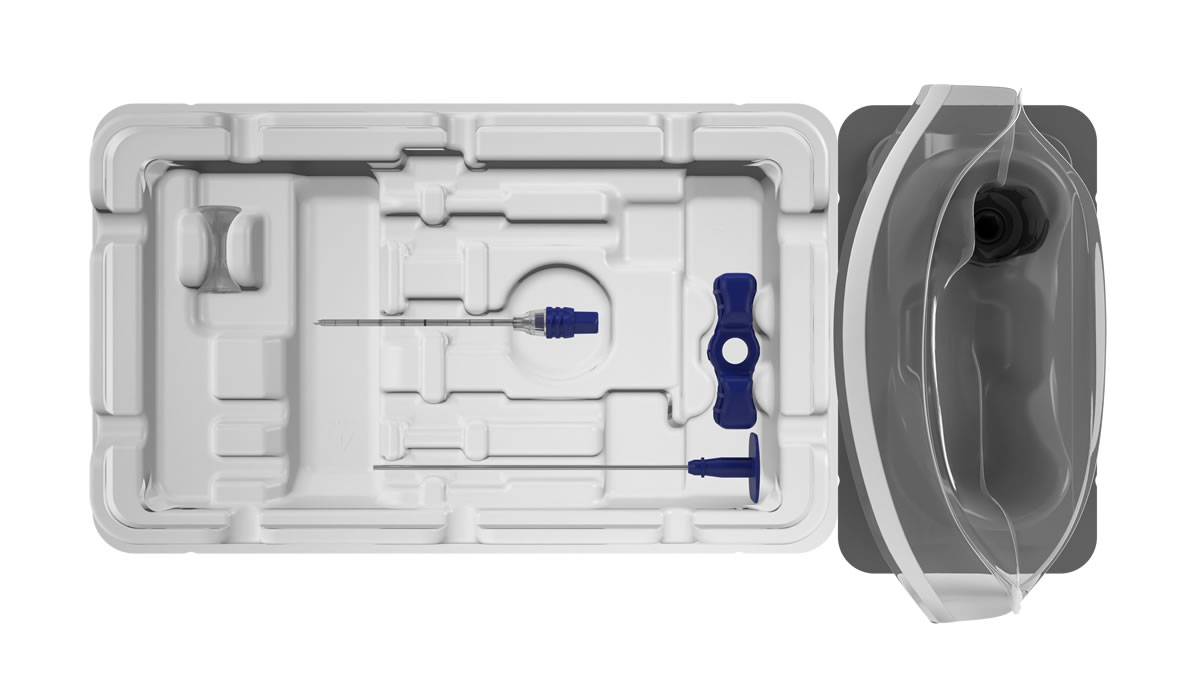

The BD Trek™ Bone Marrow Biopsy System (BD Trek™ Power Driver, BD Trek™ Bone Marrow Biopsy Kit) is intended for bone marrow aspiration and biopsy in adult and pediatric patients age 2 and older.

1. Use only BD Trek™ Biopsy Kits with the BD Trek™ Power Driver.